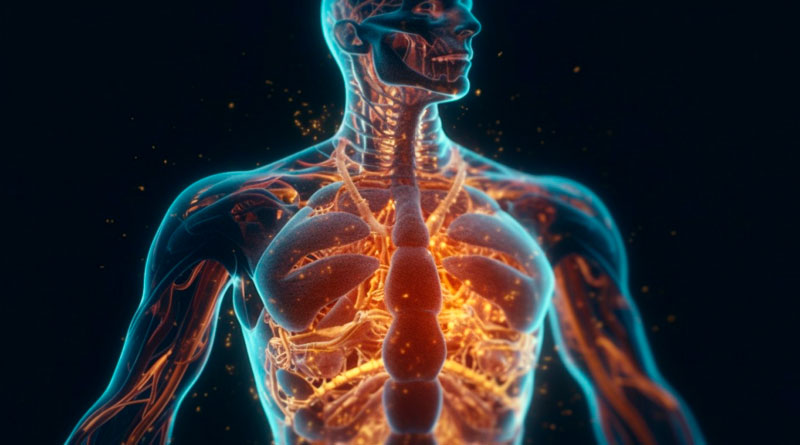

El cuerpo humano es una máquina sorprendente. A pesar de su aparente fragilidad, es fuerte y, afortunadamente, ya sea por culpa de accidentes, enfermedades u otros motivos (como malformaciones en el feto), poseemos partes del cuerpo que no necesitamos. Algunas, de hecho, nos resultan útiles en la infancia y otras, son redundantes. De ahí que sea posible perder grandes porciones de órganos vitales y sobrevivir (podemos vivir con solo medio cerebro, por ejemplo).

La evolución se toma siempre su tiempo para hacer determinados ajustes, de ahí que todos acabemos con ciertas cosas que no necesitamos. En el caso de los órganos, ya hemos visto que un ser humano puede vivir con la mitad de su órgano pensante y que incluso somos capaces de llevar una vida relativamente normal sin la presencia de algunos de ellos.

A lo mejor te sorprende pero, aunque esa máquina que es nuestro cuerpo tiene una función importante para cada una de sus partes, con el paso del tiempo y los siglos, hay algunos órganos que han perdido cierto sentido de ser, cierta funcionalidad, por lo que si no contamos con ellos, nuestro día a día no se va a ver alterado o, al menos, no en gran medida.